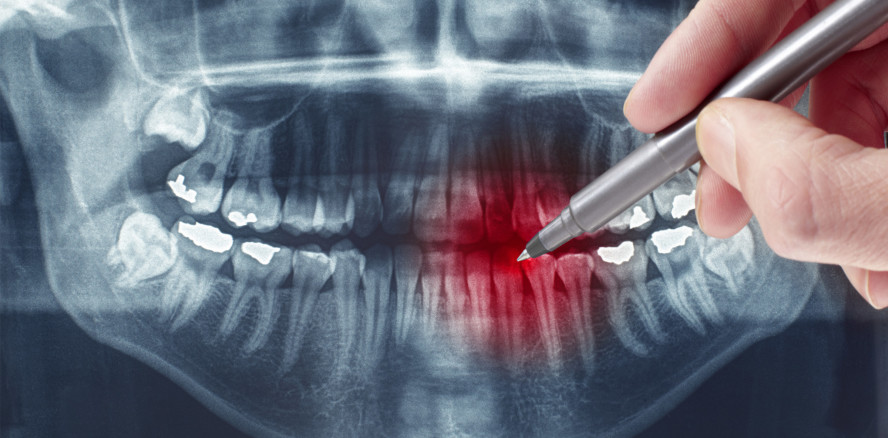

Mit der digitalen Volumentomografie (DVT) oder der digitalen Panoramaschichtaufnahme können detaillierte und aussagekräftige Röntgenaufnahmen erstellt werden, die die zahnärztliche Arbeit erleichtern. Die Röntgendiagnostik in der Zahn-, Mund- und Kieferheilkunde basiert auf einem abgestuften Konzept, und die Leitlinien definieren eindeutig Indikationen und Anwendungsmöglichkeiten dieser Röntgentechniken. Wie im Folgenden gezeigt wird, können jedoch trotz modernster Technik diagnostische Probleme auftreten.

Bei dem hier dargestellten Patientenfall bestand ein Widerspruch zwischen den klinischen und radiologischen Befunden. Sowohl die klinische Untersuchung als auch der Zahnfilm legten eine Zahnfraktur nahe. Anhand der angefertigten DVT-Aufnahme aber stellte der behandelnde Zahnarzt zunächst fest, dass die auf dem Zahnfilm sichtbare radioluzente Linie keine Frakturlinie war. Eine 45-jährige Patientin hatte einen Sportunfall. Zahn 11 war perkussionsempfindlich, druckdolent und hatte Lockerungsgrad II, die Vitalitätsprobe war negativ. Es gab keine Lippenplatzwunde. Bei dem Zahnfilm an Zahn 11 war eine radioluzente Frakturlinie deutlich erkennbar (Abb. 1). Dem behandelnden Zahnarzt alio loco lag aber auch eine ca. ein Jahr alte digitale Panoramaschichtaufnahme vor, auf der ebenfalls eine horizontale radioluzente Linie im Frontzahngebiet des Oberkiefers festzustellen war (Abb. 2). Der Verdacht lag nahe, dass es sich um ein Artefakt handelte. Die Patientin wollte unter keinen Umständen eine Wurzelkanalbehandlung oder eine Entfernung des Zahns 11, außer wenn die Fraktur ohne Zweifel nachweisbar sei. Zur weiteren Klärung der Situation ordnete der Zahnarzt eine kleinvolumige DVT-Aufnahme in Endo-Einstellung (in hoher Ortsauflösung, Kodak 9000 3D, Schnittbreite 0,076 mm, 70 kV, 10 mA, 10,68 s) an. In dieser DVT-Aufnahme war keine Frakturlinie oder Kontinuitätsunterbrechung erkennbar (Abb. 3). Aufgrund der DVT-Aufnahme wurde eine Fraktur des Zahns 11, trotz der hervorragenden Bildqualität des Zahnfilms, ausgeschlossen. Auch die Patientin sah die DVT-Aufnahme zunächst als entsprechenden Beweis an.

Bei anhaltenden Beschwerden zwei Tage später wurden die Bedingungen der ersten DVT-Aufnahme penibel reevaluiert. Die Patientin arbeitete als Assistentin in der zahnmedizinischen Radiologie. Auf der Basis ihrer beruflichen Kenntnisse hatte sie sichergehen wollen, keine Bewegungsartefakte zu verursachen. Um dieses Ziel zu erreichen, drückte sie während der Vorbereitung ihren beweglichen Zahn in eine stabile Position in Richtung Apex. Dann legte sie ihr Kinn auf die Kinnstütze und biss mit ihrem frakturierten Schneidezahn vorsichtig, aber mit Kraft in den Aufbissblock. Dies führte faktisch zu einer 100-prozentigen spaltfreien Reposition des Fragments. Damit war die Fraktur auch bei einem scharfen Bild mit Endo-Einstellung nicht mehr darstellbar. Beweisend für die Fraktur war dann die erneut durchgeführte DVT-Aufnahme, bei der nun eine seitliche Bisssperrung mit Watterollen erfolgte. Das Ergebnis war die Aufnahme entsprechend Abbildung 4 – mit einer klar erkennbaren Frakturlinie. Die Entlastung der Zahnkrone 11 ermöglichte nun den Beweis einer Zahnfraktur.

Wie im vorliegenden Beispiel deutlich wird, sollte die Diagnose unterschiedlicher Aufnahmen der zahnärztlichen Röntgendiagnostik immer kritisch und unter Einbeziehung aller Begleitumstände erfolgen. Obwohl die Verwendung der DVT- oder digitalen Panoramaschichtaufnahme-Technik oft Vorteile bei der Diagnose bietet, wie zum Beispiel das Risiko von Komplikationen zu reduzieren oder neue Informationen über Nebenbefunde zu erhalten, sind auch diese Bilddaten ohne Beachtung der klinischen Befunde nicht immer wahrheitsgetreu. Für den regelmäßigen Einsatz dieser Technologien ist ein exaktes Wissen über den ganzen Aufnahmeprozess der Bildgebung und über die Grenzen im Anwendungsbereich unabdingbar. Nur die Rekapitulation aller Aufnahmeparameter vermag scheinbar unauflösbare Widersprüche zwischen mehreren Modalitäten der zahnärztlichen Röntgenologie aufzulösen – ein Umstand, der auch ständige Aufnahme in Aktualisierungen und Weiterbildungen verdient.